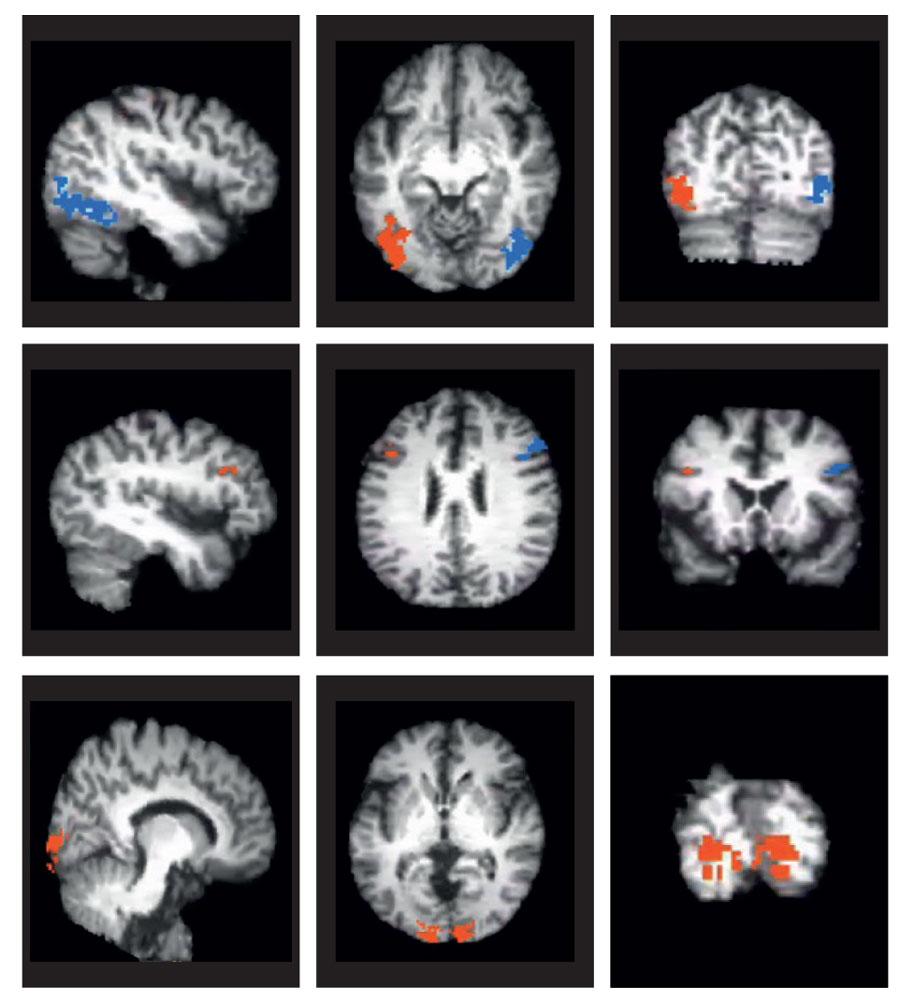

This literature review paper seeks to examine neurotransmitters and brain regions linked with schizophrenia. Schizophrenia is a severe mental illness that impacts roughly 1 in 24 million people, or 1 in 300 (.32%) people worldwide, and impairs how people think, behave, and feel. Oftentimes, individuals with schizophrenia struggle to distinguish their own thoughts from reality - an experience known as psychosis. Hallucinations and delusions are the two most common psychotic symptoms associated with the disease. Hallucinations are forms of altered perception without a specific stimulus (for instance, hearing voices that do not exist, or seeing stimuli that aren’t present). The way these forms of perception emerge is through immense amounts of dopamine production circulating through specific areas in the brain (like the frontal lobe and the ventral tegmental area). Delusions, meanwhile, are or false beliefs that lack basis in reality or facts. Understanding how certain pathways and chemicals in the brain are associated with psychosis in schizophrenia, can help shed light on how individuals are impacted by this disease and potential avenues for treatment.